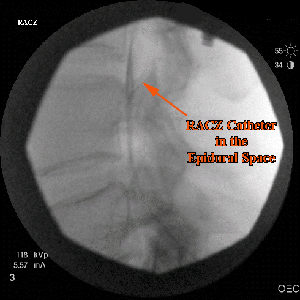

Treatment of Post Laminectomy Syndrome requires a comprehensive evaluation of the causative factors and effects on the patient’s function. Utilizing all of the diagnostic tools that are available and our expertise in providing the care, as well as patient education, we strive to assist our patients in achieving the best possible outcome that will lead to improved function as well as improved quality of life. What is the Racz Catheter Procedure (Epidural Neurolysis)? Racz CatheterThe Racz Catheter Procedure (Epidural Neurolysis) is used to release some of the scar tissue from around entrapped nerves in the epidural space of the spine, so that medications such as cortisone can reach the affected areas. It is used to decrease the pain caused by the scarring. This procedure is named for the physician who pioneered it, Dr. Gabor Racz. Dr. Barr had the good fortune to train directly under Dr. Racz. What causes epidural scarring? Epidural scarring most often occurs from bleeding into the epidural space following back surgery and the subsequent healing process where epidural fat is replaced with fibrotic tissue. It is a natural occurrence following surgical intervention. Sometimes scarring can also occur when a disc ruptures and its contents leak out. How long does the procedure take? The procedure generally takes between 30 and 60 minutes. It can be done once, or in a series of up to three injections in a twelve-month period. A catheter is inserted in the caudal epidural space and steered up to the area of scarring. This is done in our fluoroscopy suites under sterile conditions with IV sedation. What is actually injected? The injection consists of the following:

Racz Catheter EpiduralWill the injection hurt? The procedure involves inserting a needle through skin and deeper tissues. There is some discomfort involved, which will feel like getting a tetanus shot or skin prick. The skin and deeper tissues are numbed with a local anesthetic prior to insertion of the spinal needle and catheter. Will I receive any sedation for this procedure? This procedure is done under a combination of local anesthesia and IV sedation, which makes the procedure easy to tolerate. The amount of sedation given will generally depend upon the patient’s tolerance. Communication with the patient during the procedure is important to help assess the proper placement of the catheter. What should I expect during and after the procedure? This procedure is done with the patient lying on his or her stomach. The patient is monitored with EKG, blood pressure cuff, and blood oxygen-monitoring devices. The skin is prepped with an antiseptic solution before the procedure is performed under X-ray guidance (fluoroscopy), which is used to assist the placement of the catheter and perform the epidurogram. After the procedure you will be able to gradually get up and walk into the recovery area. Your legs might feel slightly heavy or numb. You may also notice that your pain may be gone or significantly reduced. This is due to the local anesthetic injected. Although this will last only for a few hours, driving is prohibited following the procedure that day. Racz Catheter ProcedureWhen can I return to work? Unless there are complications, you should be able to return to work the day after the procedure. The most common thing you may feel is a sore back. How long will the effects of the medication last? The immediate effect is usually from the local anesthetic that was injected. This effect will usually wear off in a few hours. The cortisone usually starts working in about 3 to 7 days and the effect can last for several days up to a few months. Racz Catheter Pain ReliefWill the Racz procedure (Epidural Neurolysis) help me? It is very difficult to predict if the procedure will help you or not. Overall, patients who have recent scarring, such as scarring following recent back surgery, will respond better than those with more long-term scarring. Patients with leg pain and low back pain often report excellent relief of leg pain and some relief of low back pain. What are the risks and side effects? Overall, this procedure is safe. However, with any procedure there are risks, side effects, and the possibility of complications. Fortunately, the serious side effects and complications are uncommon. Risks and side effects may include the following: